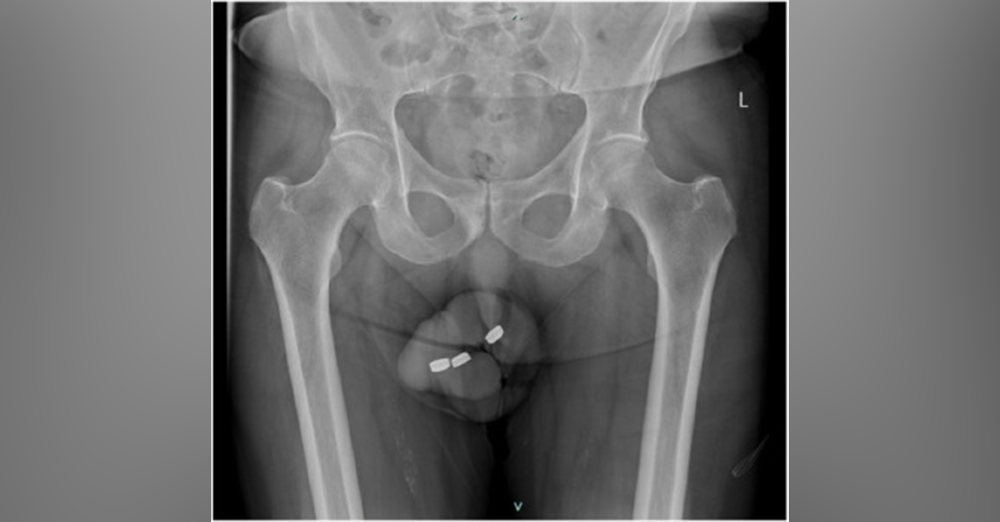

À l'âge de 73 ans, un homme s'est retrouvé dans une situation critique après avoir inséré trois piles bouton dans son urètre, une pratique à laquelle il s'était déjà adonné sans problème par le passé pour atteindre une satisfaction sexuelle.

Confronté à des difficultés majeures pour les retirer, il s'est résigné à se rendre aux urgences 24 heures plus tard, présentant des symptômes douloureux et des troubles urinaires significatifs.

Son dossier médical faisait état de plusieurs conditions chroniques, dont le diabète de type 2 et l'hypertension, ainsi que d'une dysfonction érectile traitée par diverses méthodes. À l'examen clinique, les médecins ont découvert un pénis douloureux, œdémateux et brûlé par le matériau corrosif des piles, imposant une intervention chirurgicale immédiate sous anesthésie générale.

Malgré la complexité de l'opération, due à l'érosion causée par les piles et les dommages étendus à l'urètre, les batteries ont été retirées avec succès.

Cependant, la situation s'est aggravée dix jours après sa sortie de l'hôpital, lorsque l'homme a dû être hospitalisé à nouveau en raison d'une infection sévère et d'une nécrose de l'urètre. Les dommages étant irréversibles, les médecins ont conseillé au patient d'avoir recours à une greffe de pénis.